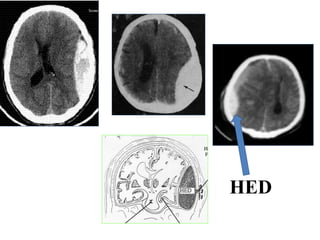

Hématome sous dural : H.S.D

C’est une collection de sang extra axiale péri

cérébrale entre la dure mère et l’arachnoide

secondaire à une plaie d’une veine corticale

• Il est aigu , subaigu ou chronique remontant à

plusieurs jours voire plusieurs mois

• S’accompagne de troubles neurologiques

RX CRANE :

crâne normal

syndrome d’HTIC parfois calcifications: lame ou plaque

calcifiée (HSD CHRONIQUE)

• TDM :

Stade de début: formation spontanément

hyperdense en croissant

Stade sub Aigu: aspect isodense

Stade chronique: hypodense (plusieurs

semaines après le traumatisme )

Recherche de signes d’engagement .

HSD aigu

HSD Sub Aigu

HSD Chronique